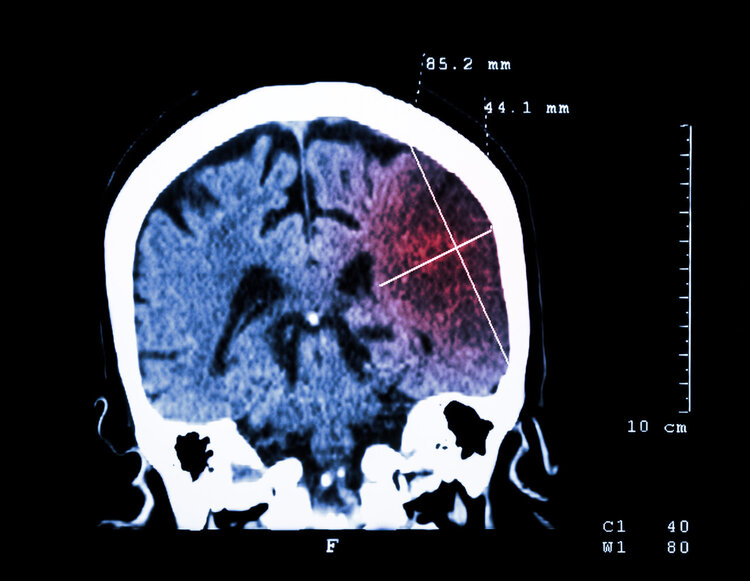

大脑作为人体重要的器官之一,指挥着人体全身的动作,一旦发生堵塞出现脑梗,会出现各种的症状,严重的还会危及生命。虽然人们的物质生活得到了改善,但是患脑梗的人数一直居高不下,而且呈现年轻化的趋势,为什么中国的脑梗发病率一直居高不下呢?

大脑作为人体重要的器官,能够支配人的各种行为,一旦发生脑梗,会引发各种的症状。据统计中国的脑梗发病率一直很高,而且呈现年轻化的趋势,这主要与长期熬夜、吸烟、喝酒等的不良习惯有关,对于高风险人群要通过膳食结合强化补充叶酸的方法来降低卒中风险。